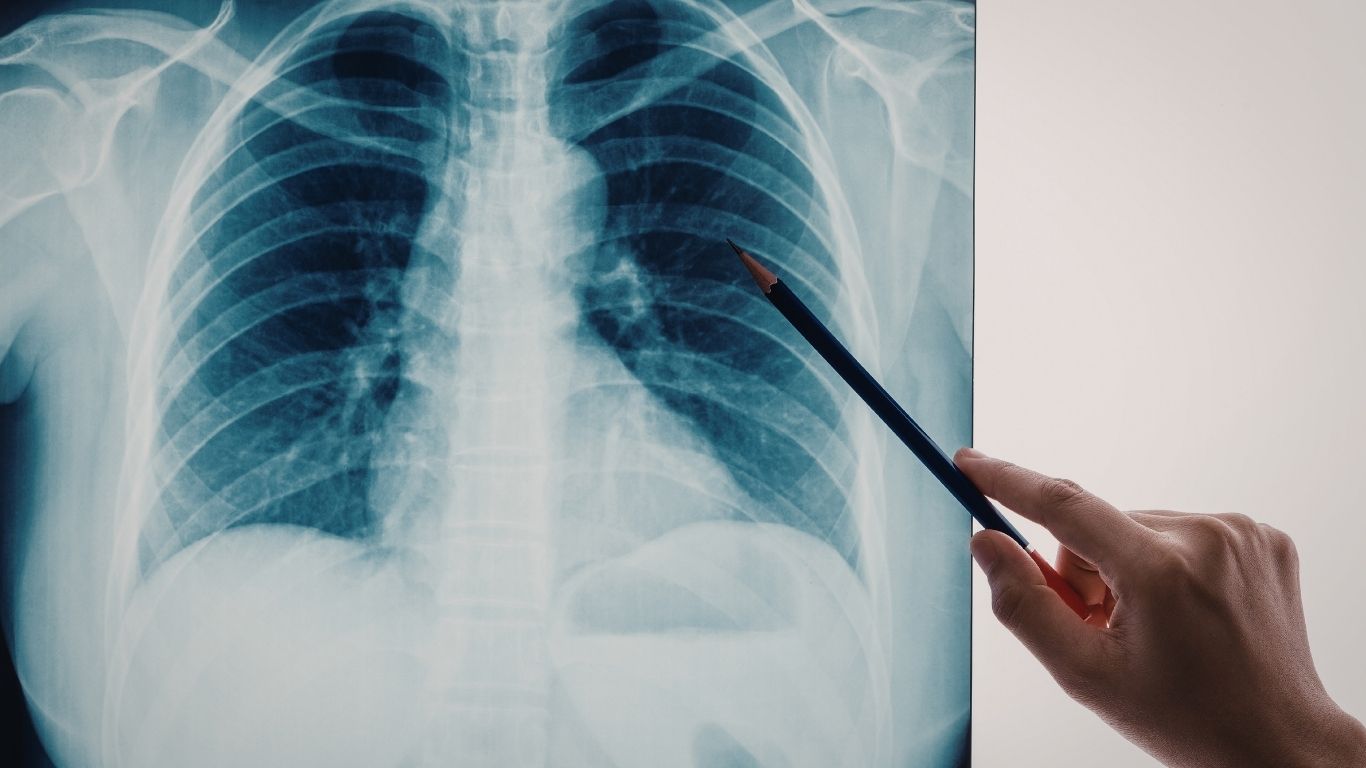

NỐT MỜ PHỔI: KHI NÀO CẦN ĐI KHÁM?

Nốt mờ phổi là thuật ngữ dùng để chỉ một vùng tổn thương có hình tròn hoặc bầu dục, đường kính ≤ 3 cm, xuất hiện trong nhu mô phổi trên phim X-quang hoặc chụp cắt lớp vi tính (CT).

Nếu tổn thương lớn hơn 3 cm, thường được gọi là khối u phổi thay vì nốt.

Phát hiện nốt mờ phổi khá thường gặp trong quá trình khám sức khỏe định kỳ, kiểm tra bệnh hô hấp hoặc tầm soát ung thư phổi. Hầu hết bệnh nhân không có triệu chứng khi được phát hiện.